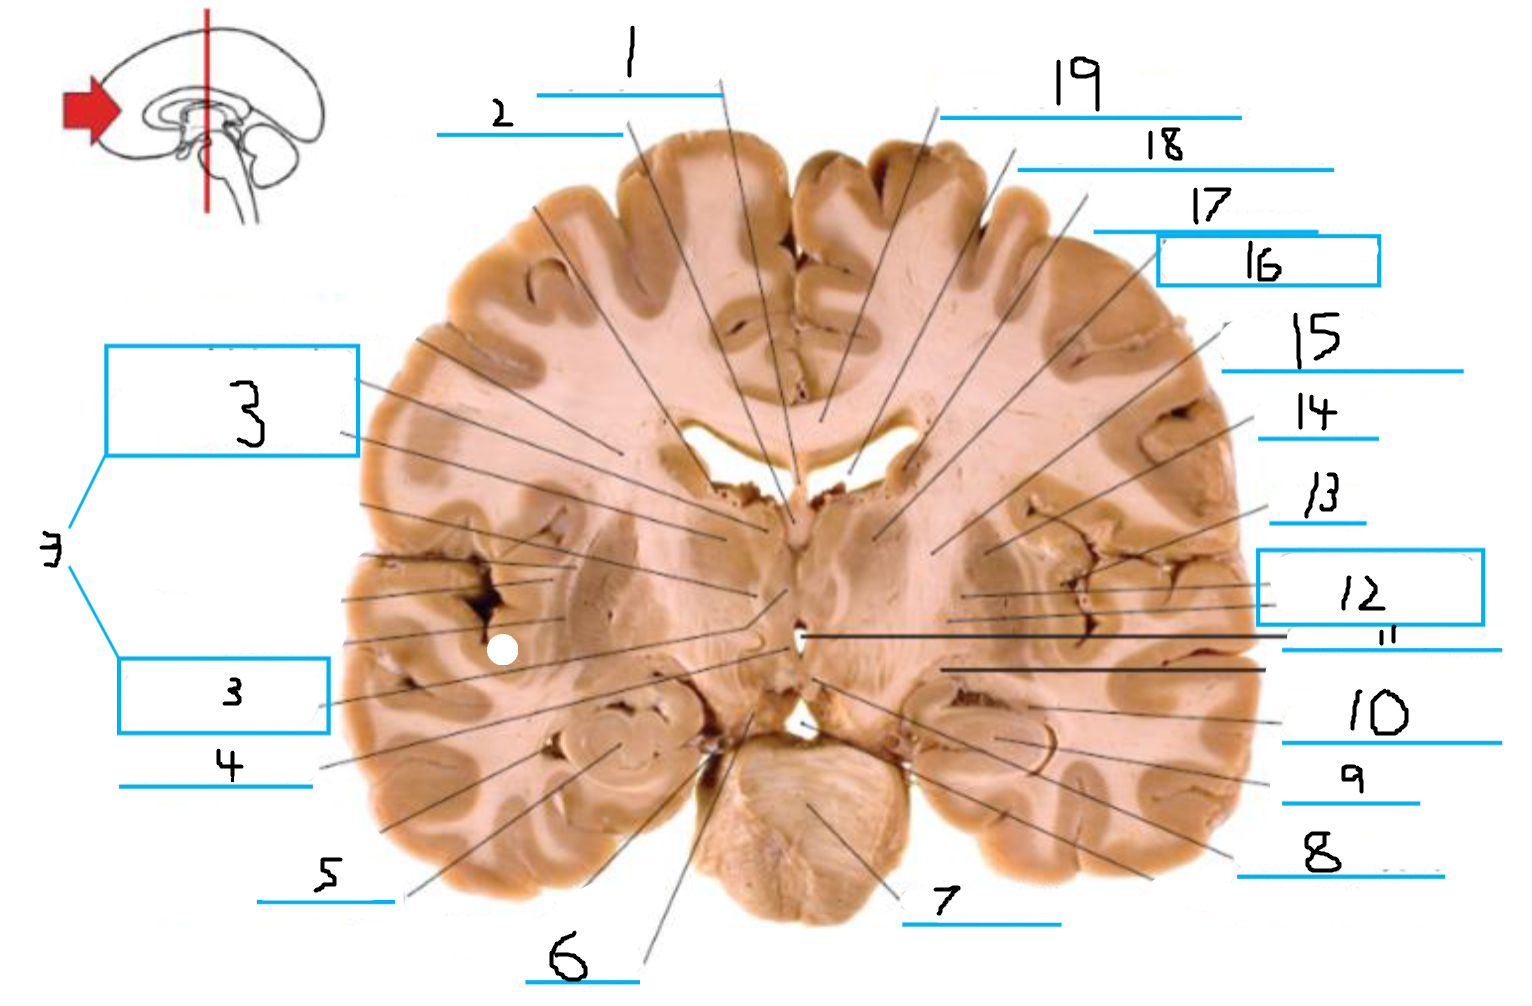

#1 is the:

Cingulate Gyrus

#2 is the:

Septum Pellucidum

#3 is the:

Lateral Ventricle

#4, #7, and #12 is the:

Fornix

#5 is the:

Third Ventricle

#6 is the:

Anterior Commissure

#8 and #11 is the:

Amygdala

#9 is the:

Hypothalamus

#10 is the:

Mammillary Body

#13 is the:

Insula

#14 is the:

Globus Pallidus

#15 is the:

Putamen

#16 is the:

Internal Capsule

#17 is the:

Caudate

#18 is the:

Corpus Callosum